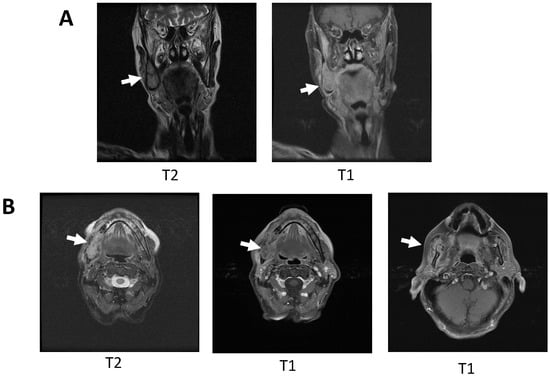

2. Results

2.1. Clinical and Histological Manifestations of the Tumors

4.2. Magnetic Resonance Imaging